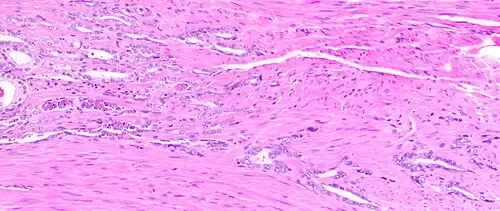

The prostate consists of glandular and connective tissue.[2] Tall column-shaped cells form the lining (the epithelium) of the glands.[2] These form one layer or may be pseudostratified.[4] The epithelium is highly variable and areas of low cuboidal or flat cells can also be present, with transitional epithelium in the outer regions of the longer ducts.[10] Basal cells surround the luminal epithelial cells in benign glands. The glands are formed as many follicles, which drain into canals and subsequently 12–20 main ducts, These in turn drain into the urethra as it passes through the prostate.[4] There are also a small amount of flat cells, which sit next to the basement membranes of glands, and act as stem cells.[2]

The connective tissue of the prostate is made up of fibrous tissue and smooth muscle.[2] The fibrous tissue separates the gland into lobules.[2] It also sits between the glands and is composed of randomly orientated smooth-muscle bundles that are continuous with the bladder.[11]

Over time, thickened secretions called corpora amylacea accumulate in the gland.[2]